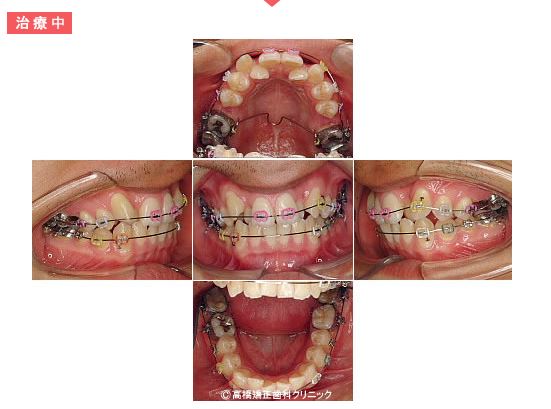

治療中

奥歯の位置を調整しながら前歯にも装置を付けていきます。

歯列内にスペースができています。